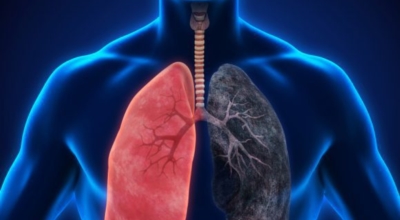

폐에 발생된 악성 종양을 말하며 오랜 기간 흡연해온 남성들에서 발병률이 높고 요즈음 각종 환경적인 요인의 영향과 간접흡연으로 흡연하지 않는 여성에서도 많이 발생하고 있습니다. 증상을 느껴 병원을 찾았을 때는 수술하기 늦은 경우가 많아 사망 가능성이 매우 높은 암입니다. 폐 자체에서 발생하거나 다른 장기에서 발생된 암이 폐로 전이되어 발생하기도 하고 특별한 초기 증상이 없는 경우가 많고 암이 진행된 후에도 공통적인 감기 증상인 기침과 가래 외의 특이 증상이 나타나지않아 증상만으로는 진단이 쉽지 않습니다.

폐암의 공통 위험요소로 손꼽히는 이유가 되는 것으로 흡연이 있어요. 흡연자는 비흡연자에 대조해 십몇 배는 더 폐암 발병확률이 높다고 하며 어느정도 기간 동안 흡연했는지에 따라 폐암 발생확률은 더욱 더 높아집니다. 흡연자라고 해도 금연을 하게 되면 폐암 발병확률이 빠르게 낮아진다고 하니 폐암이 걱정되신다면 가장 먼저 금연은 필수입니다.